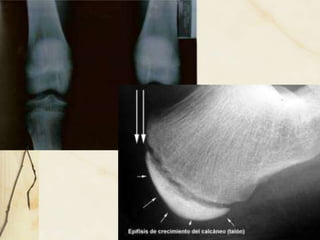

SINCONDROSIS

• UNION POR CARTILAGO HIALINO

• SE OBERVAN EN LA ETAPA DE

CRECIMIENTO

• 1° ARTICULACION ESTERNOCOSTAL